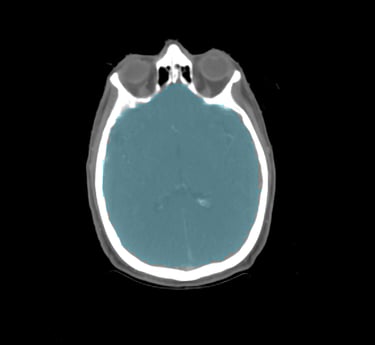

Head & Neck

Choose from a combined structure volume including BrainStem, Brain, Chaism, Mandible, Optic nerves Trachea and many more, or choose individual split sub-levels.